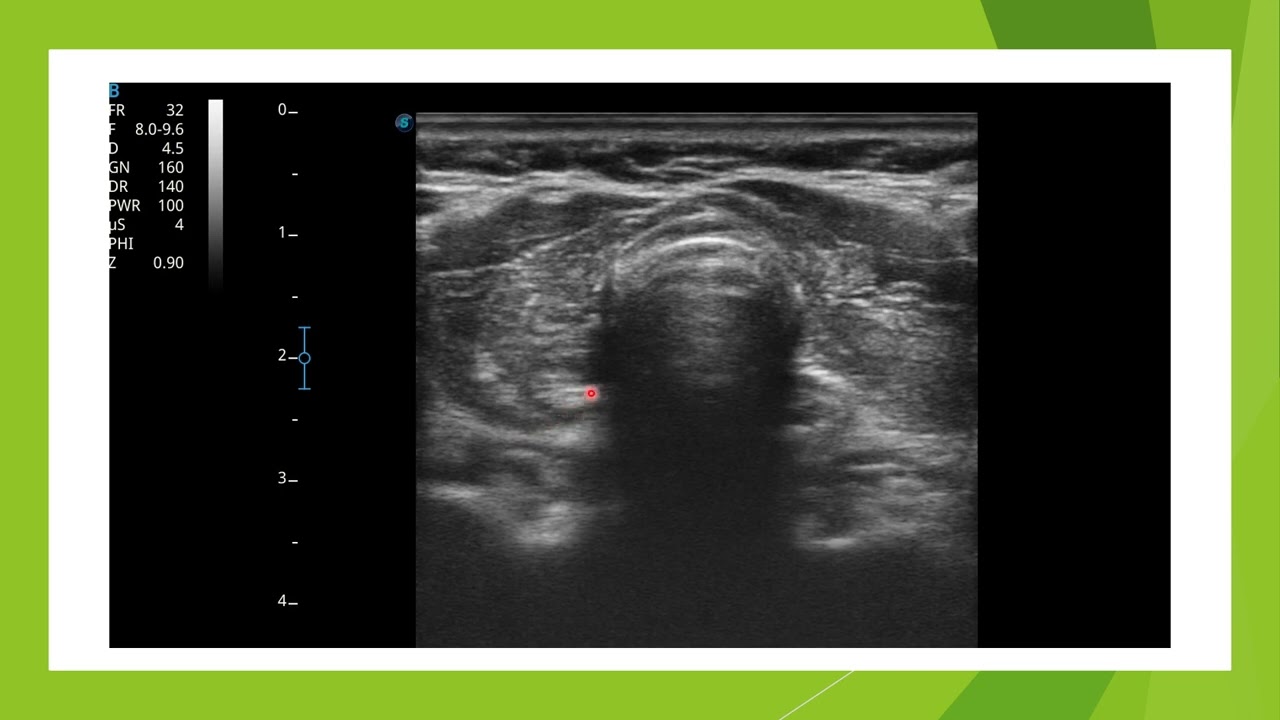

Echographie d'une Thyroidite de Hashimoto

Aspect typique d'une thyroidite autoimmune de Hashimoto en échographie chez une femme de 56 ans. Anticorps anti thyroglobuline positifs et anticorps anti TPO négatifs.